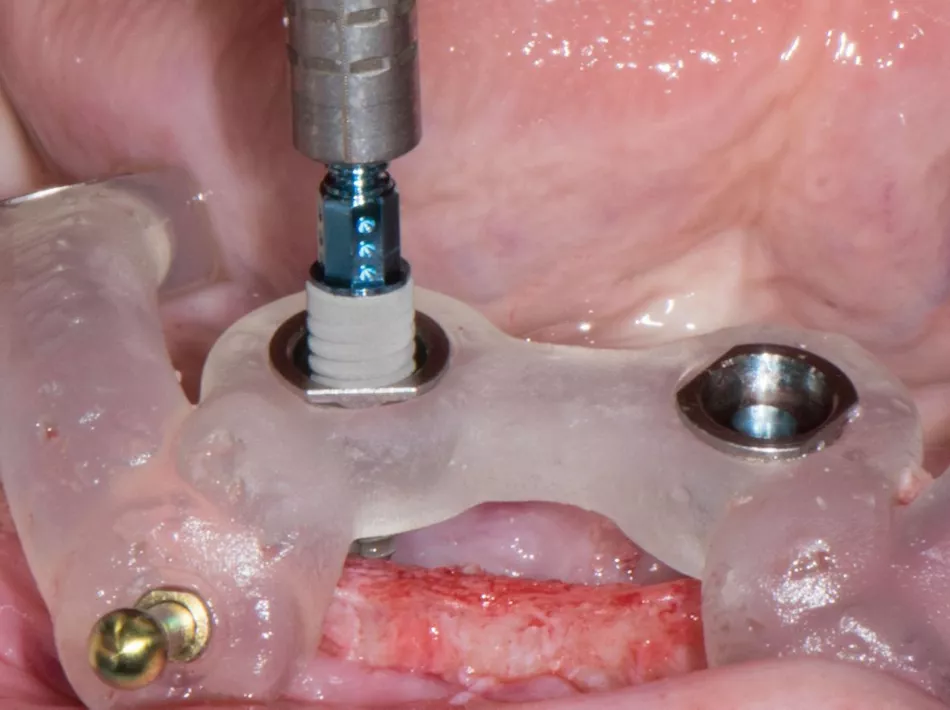

Fig. 3: The Straumann® TLX implant combines a smooth transgingival collar with an aggressive thread design optimized for high primary stability

(picture courtesy of Dr Mario Rocuzzo, see full case report here).